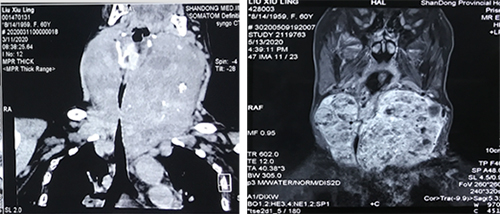

患者为60岁女性,20余年前曾行结节性甲状腺肿切除,随后出现结节性毒性甲状腺肿,同时患有房颤、心衰、乳腺癌等多种疾病。近一年来,患者甲状腺增生明显,严重压迫颈段气管,最狭窄处直径仅为4mm,继发呼吸困难、心衰,一度病危。患者多方求医,但因其病情复杂、手术难度、风险巨大,多所三甲医院均表示无法手术。患者辗转找到我院耳鼻咽喉头颈外科许风雷、夏明手术团队。两位医生组织包括内分泌科、麻醉科、心外科、重症医学科等学科的MDT,针对患者无法插管、心肺功能差的复杂病情,制定了手术方案:先期由内分泌科主任医师李茵茵为患者治疗,控制患者甲亢,改善心肺功能,术中ECMO技术支持,完整切除巨大甲状腺肿。

经过术前充分准备,患者病情趋于稳定。5月18日,进行手术治疗。心外科许崇恩、张文龙团队率先行清醒状态下ECMO上机,麻醉科徐艳冰团队实施全麻,细管辅助通气,重症医学一科张琳医生全程监护甲状腺素水平,耳鼻咽喉头颈外科副主任医师夏明实施手术。历经4小时的努力,完整切除血供非常丰富的巨大颈部甲状腺肿,在保留胸骨的情况下切除胸骨后段上纵膈甲状腺肿,肿物重量共518g,解除气管压迫,保留双侧喉返神经、甲状旁腺,同时行预防性气管切开。术后患者转入重症医学一科进行对症处理。患者第二天经口进食,身体各项机能恢复,目前已康复出院。